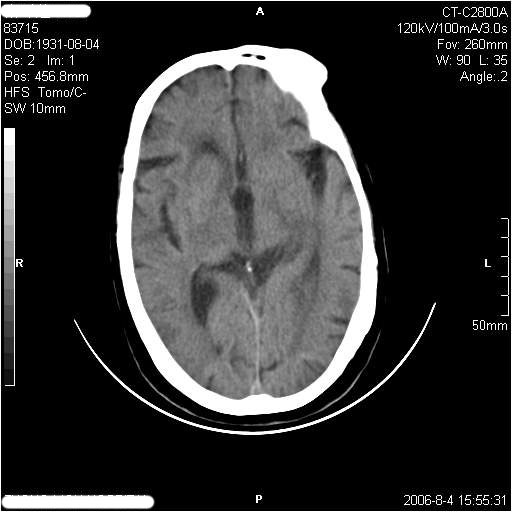

左侧偏瘫3天.

有摔倒外伤史,另看右侧灰白质界限.

1、该患者从脑实质表现情况看应该年龄较大了,双侧基底节区多发斑片状低密度灶,侧脑室旁白质密度减低,各脑室腔扩大,脑沟裂增宽加深,以上改变符合:皮层下动脉硬化性脑病。

2、上纵裂右侧梭形条状高密度影阴,边缘模糊,周围水肿带环绕,右侧脑室受压变形,有摔倒外伤史,多考虑:纵裂硬膜下血肿。